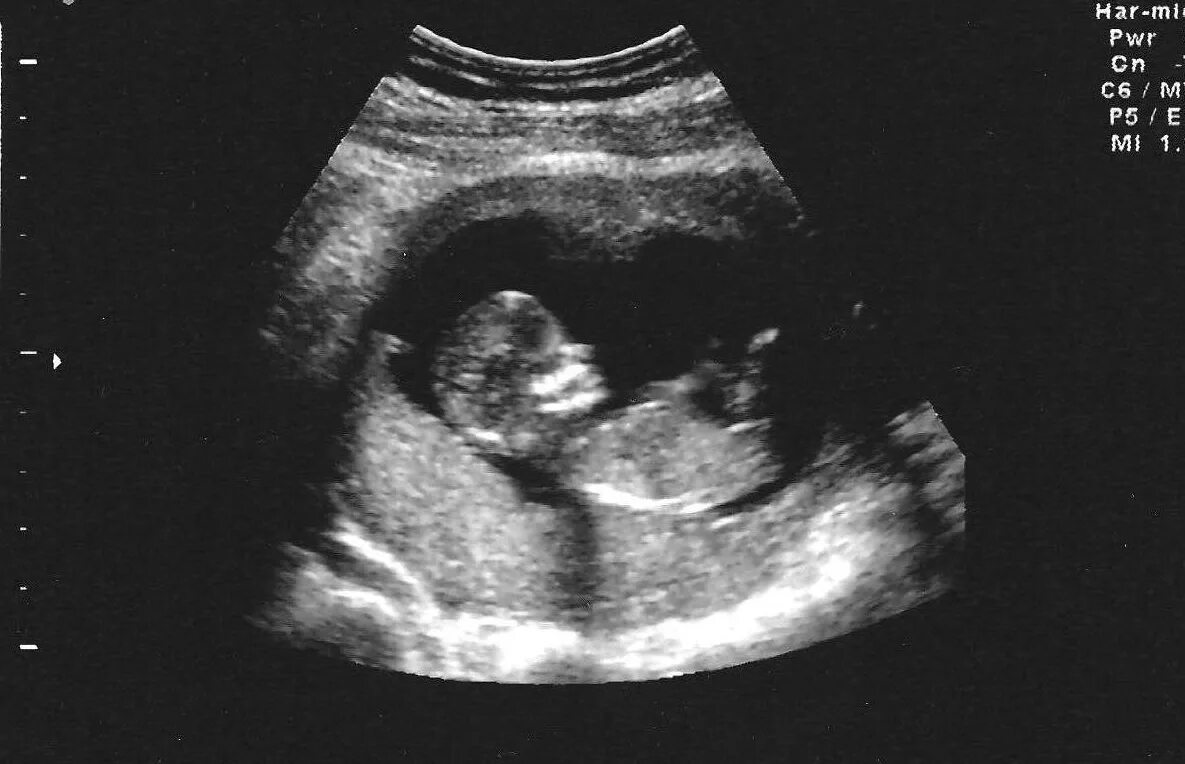

10 неделя пол ребенка